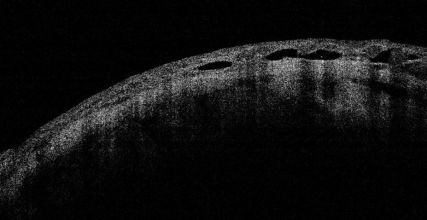

Senile Retinoschisis[20]

There is a splitting of retinal layers at the outer plexiform layer, usually in the inferotemporal peripheral fundus in elderly hyperopic patients. On the contrary, retinal detachment shows separation of the neurosensory retina and the retinal pigment epithelium.